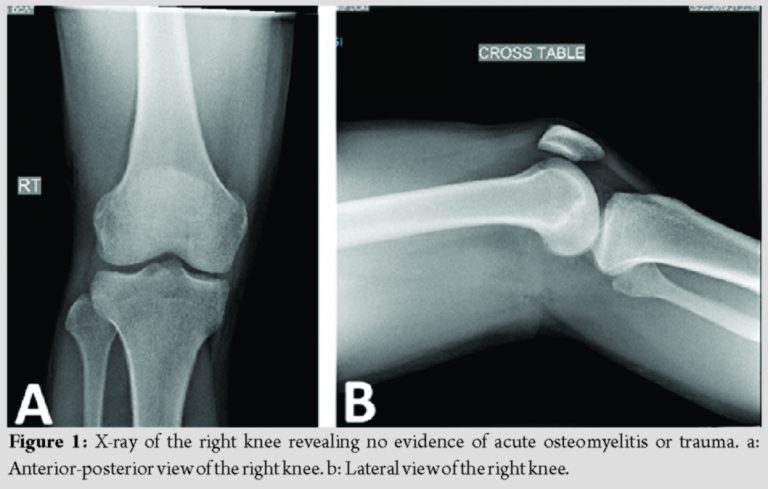

At presentation, the patient stated that this episode did not resolve with rest or anti-inflammatory medication. He reported the drainage had been ongoing for 2 weeks and appeared to come from a punctum in the center of the swelling, but denied any fever, chills, sharp pain, change in sensation, or restriction in active or passive range of motion. X-ray showed no acute OM or fractures (Fig. 1a and b). Magnetic resonance imaging (MRI) of the knee revealed 6.8 × 5.3 × 8.5cm septated fluid collection consistent with a large abscess extending from the subcutaneous adipose tissue along the lateral aspect of the thigh through a perforation in the fascia posterior to the vastus lateralis and tensor fascia lata and anterior to the biceps femoris (Fig. 2a-d). The fluid collection also extended deep between the muscle bellies to the level of the posterior lateral cortex of the distal femoral diaphysis. Diffuse soft-tissue edema was visualized; however, no periosteal or marrow edema was present, confirming the absence of acute OM (Fig. 3a and b).